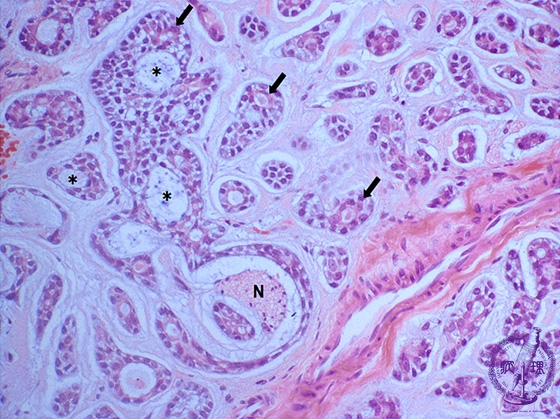

Microscopic finding (HE stain, high-power view):There are two kinds of cavities in the cribriform nests, true lumens (arrows) and pseudocysts (*). The true lumens and pseudocysts are lined by eosinophilic glandular cells and neoplastic myoepithelial cells/basaloid cells with scant cytoplasm, respectively. Perineural invasion (N) is observed.